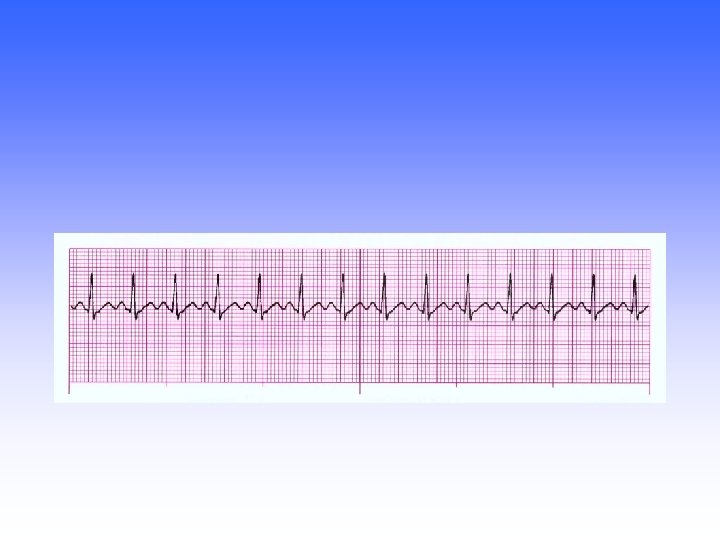

Mobitz II Regular: regular (QRS & P) P-wave: present, upright PRI: constant QRS: <

Mobitz II Regular: regular (QRS & P) P-wave: present, upright PRI: constant QRS: < 0. 12 sec